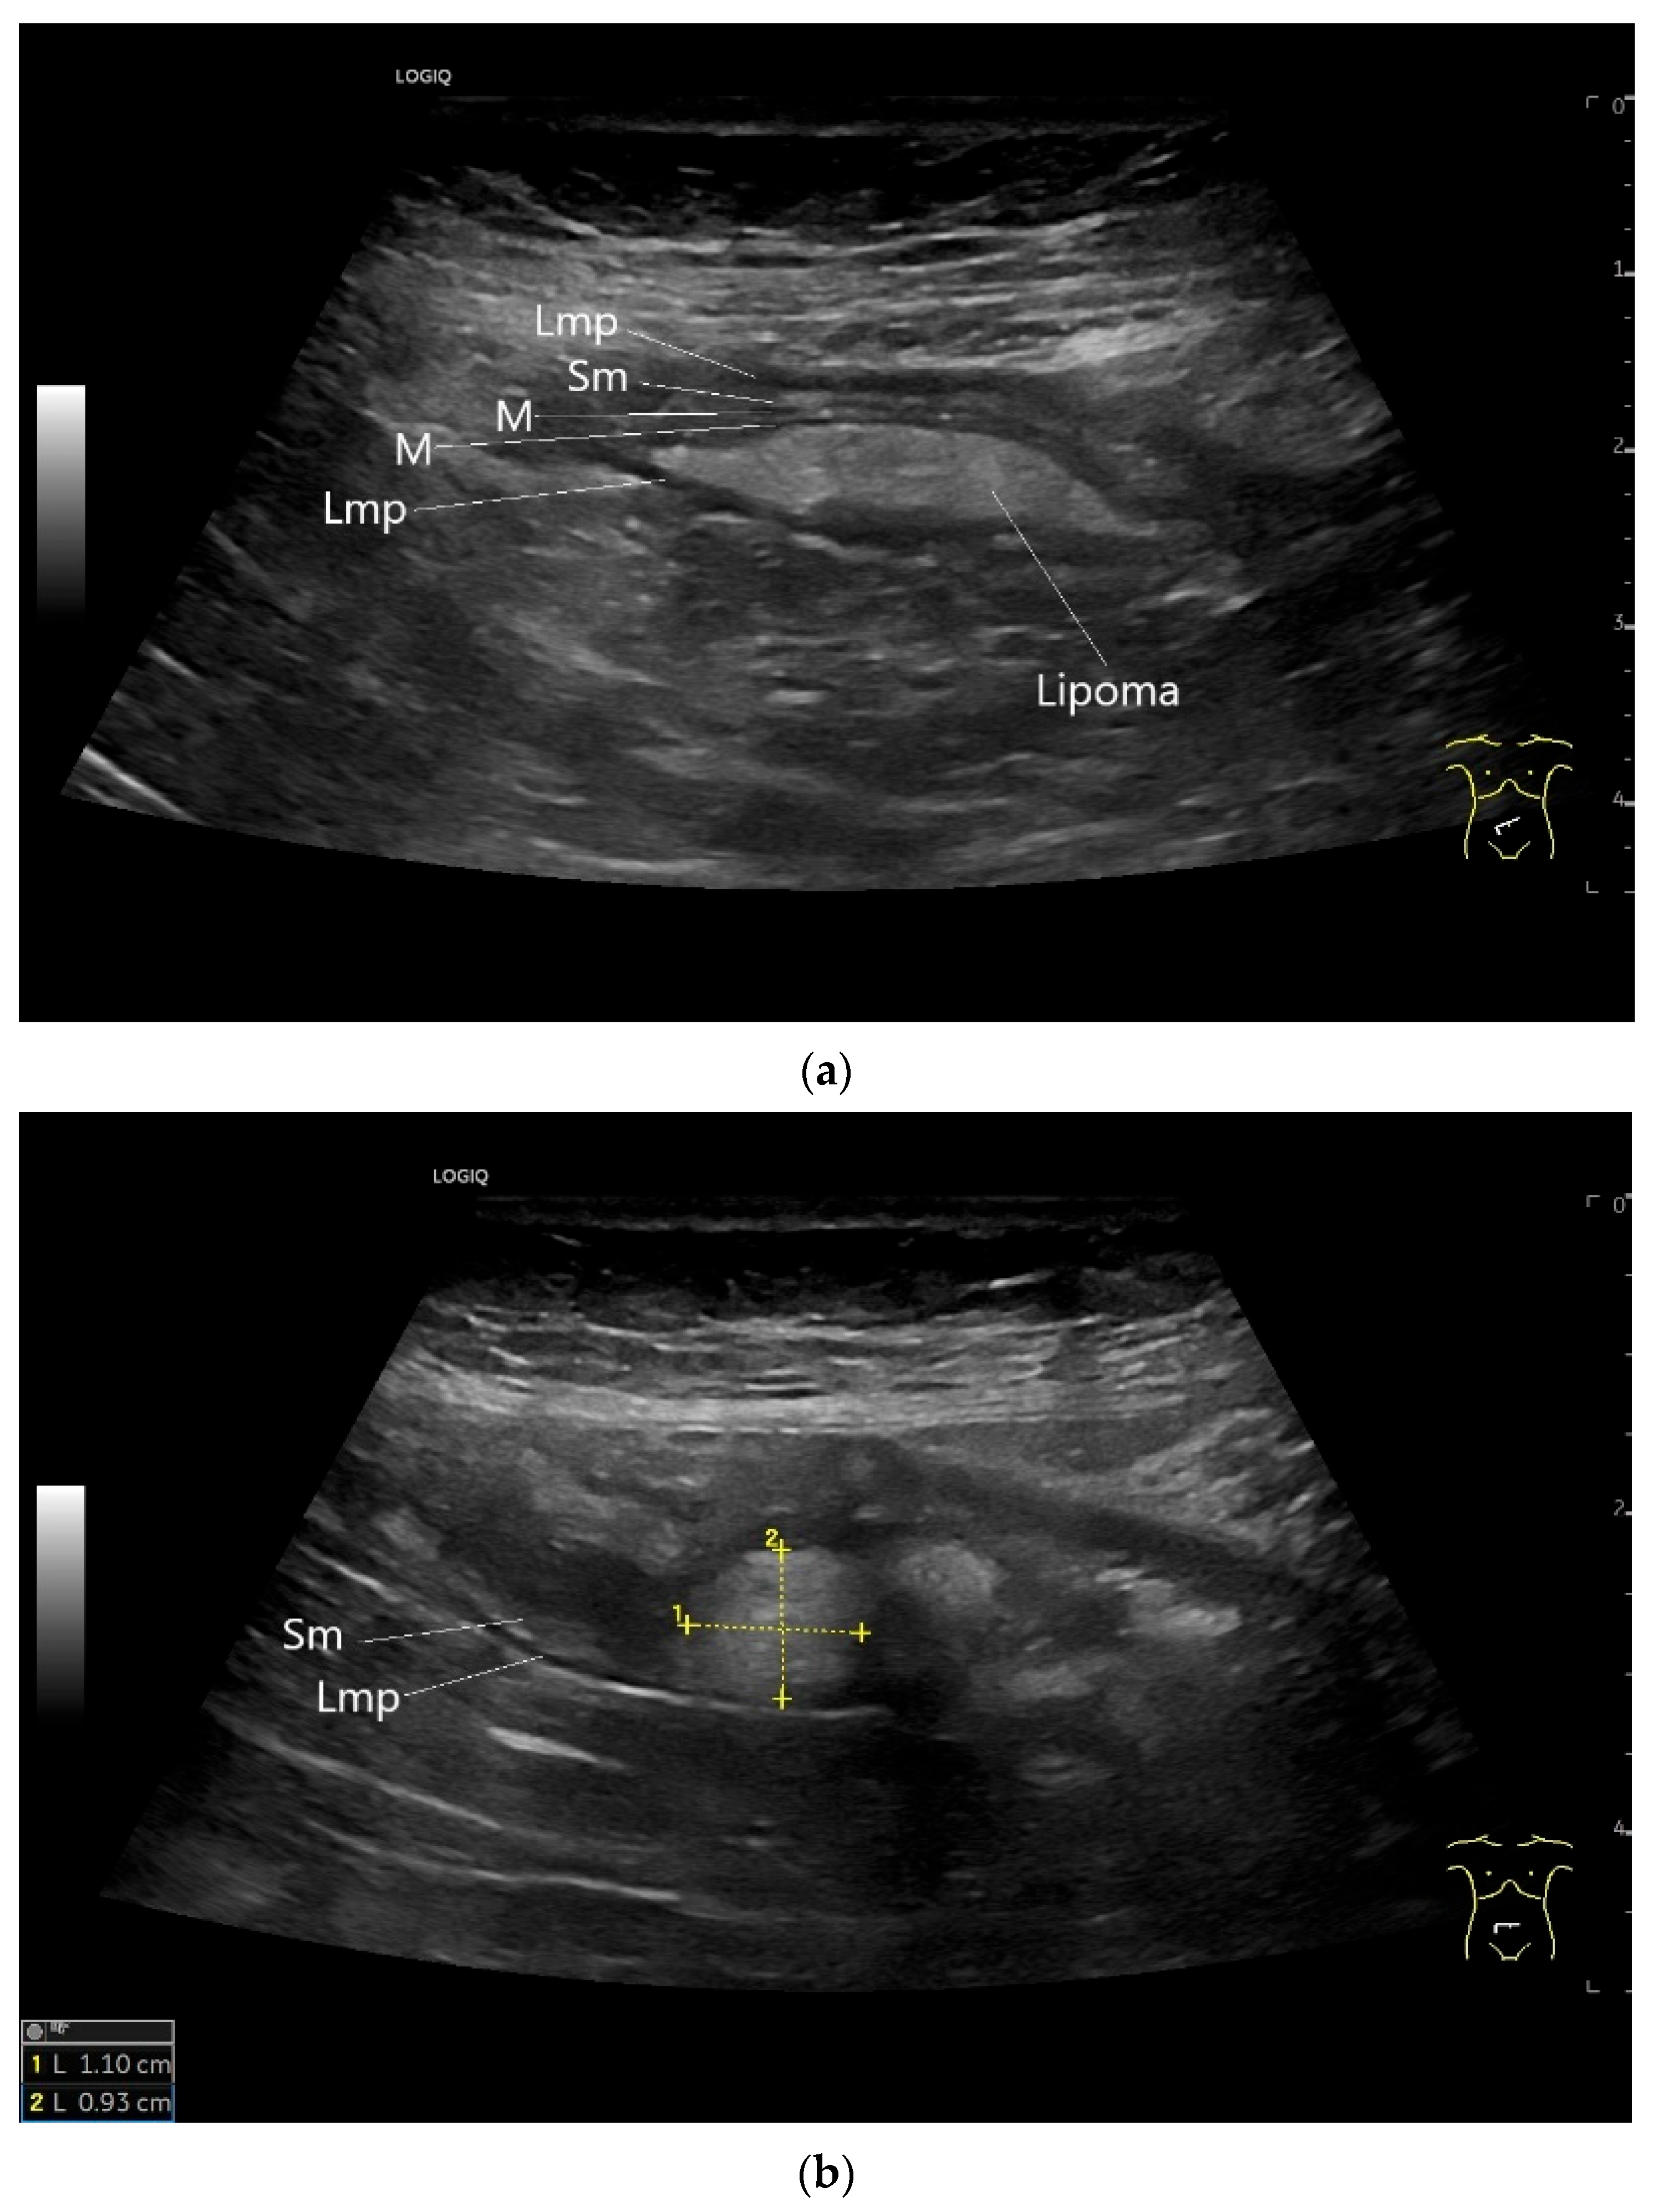

Lipomas are benign, smoothly bordered oval/round lipomatous lesions that usually originate in the submucosa. They appear homogeneous and hyperechoic on EUS and US (Figure 16). They are rare in the small intestine.

Figure 16.

Lipoma in the ileum. An incidental finding reveals a homogeneous hyperechoic lesion in the right lower abdomen. This can be attributed to the ileum. The mass is shown in longitudinal section (a) and cross-section (b). The longitudinal section (b) shows the layer classification. M—mucosa; Sm—submucosa; Lmp—muscularis propria layer.